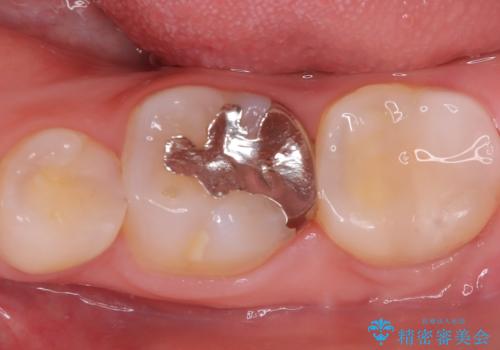

- 初診時にお口の中をチェックしたところ虫歯があり、大きさから部分的な詰め物のお話をしました。材料の特性を説明し、再び虫歯になりにくいセラミックインレーを選択されました。

セラミックインレー接着時にはラバーダム防湿を行いました。